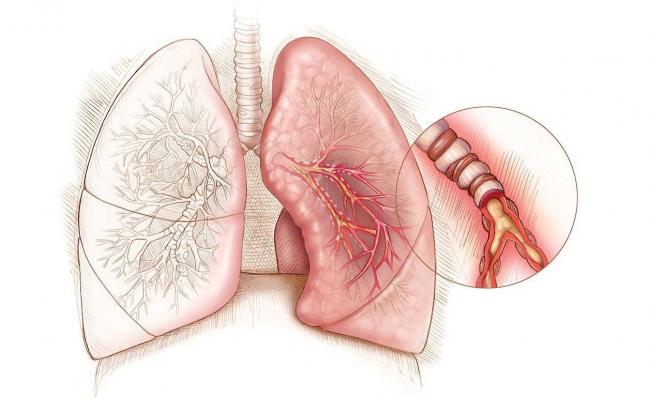

Бронхоэктатическая болезнь характеризуется возникновением в полости бронхов альвеолярных расширений пузырькового вида. Подобные пузырьки заполнены серозной жидкостью, кровью и гноем. При интенсивном кашле эктазы разрываются, и их содержимое изливается, эвакуируясь из организма. Отсюда присутствие крови в мокроте без температуры. Гипертермия наблюдаюется в очень редких случаях.

2. Метод бронхоскопии целесообразен для диагностики бронхоэктатической болезни, рака лёгких. Суть метода состоит в определении изменений в просвете бронха (при опухолях, патологических расширениях бронха, просвет сужается, и на снимке это заметно). С помощью эндоскопического инструмента бронхоскопа можно: